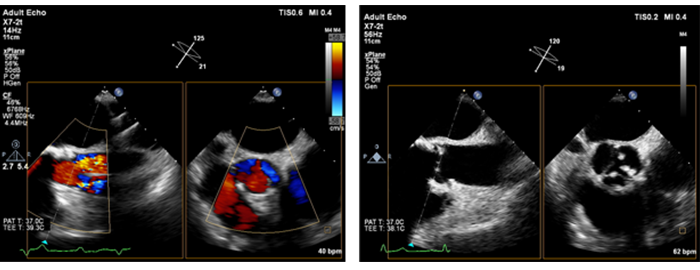

Mit der Live xPlane Bildgebung können zwei Ebenen gleichzeitig mit voller Auflösung und dadurch doppelt so viele klinische Informationen wie bei der herkömmlichen 2D-Bildgebung in derselben Zeit erfasst werden.

Bei Herzuntersuchungen ermöglicht die Live xPlane Bildgebung die gleichzeitige Erfassung von zwei Ebenen desselben Herzschlags und so auch die schnelle, zuverlässige Erfassung wichtiger Informationen.